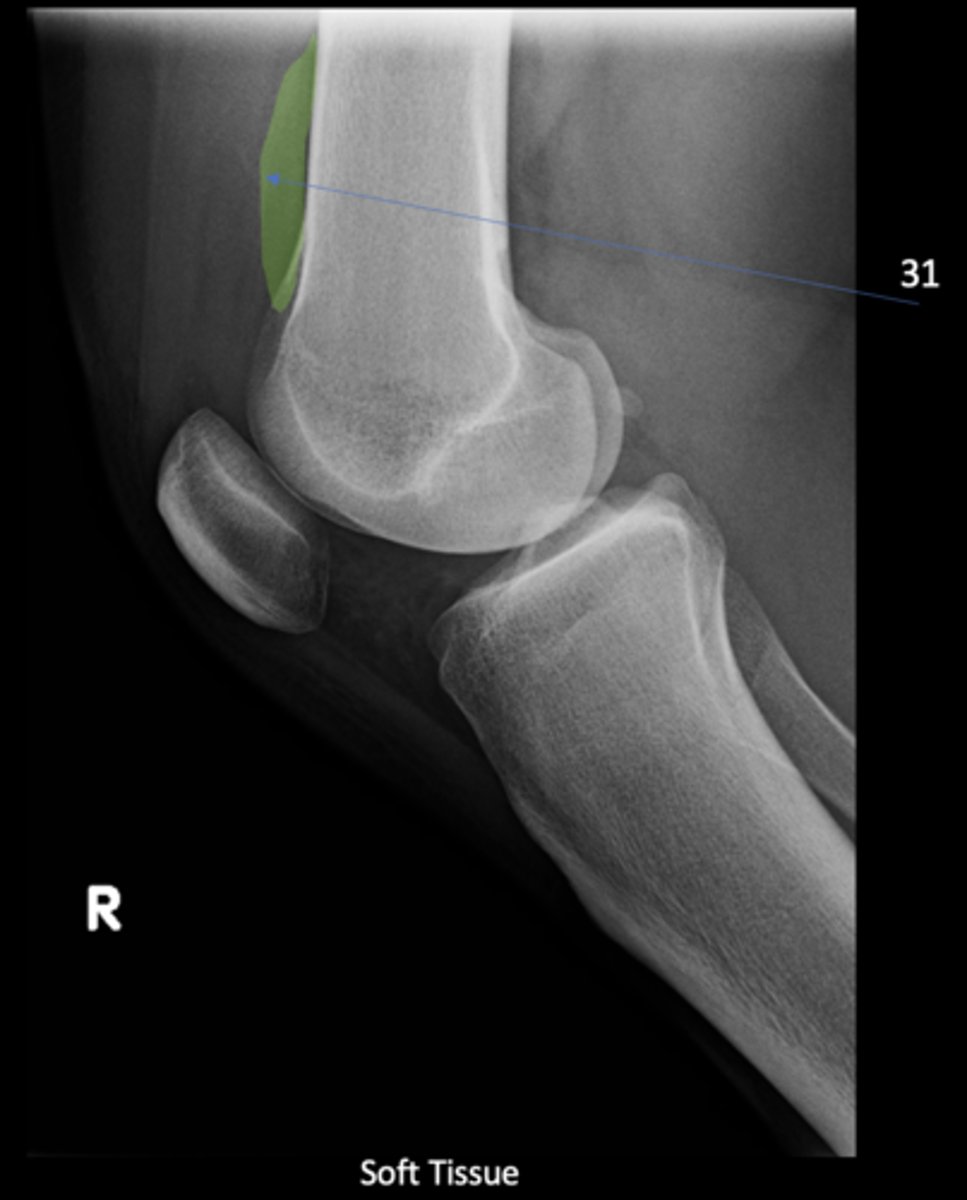

Quadriceps tendon

ID 30

<p>ID 30</p>

Prefemoral fat pad

ID 31

<p>ID 31</p>

Suprapatellar pouch

ID 32

<p>ID 32</p>